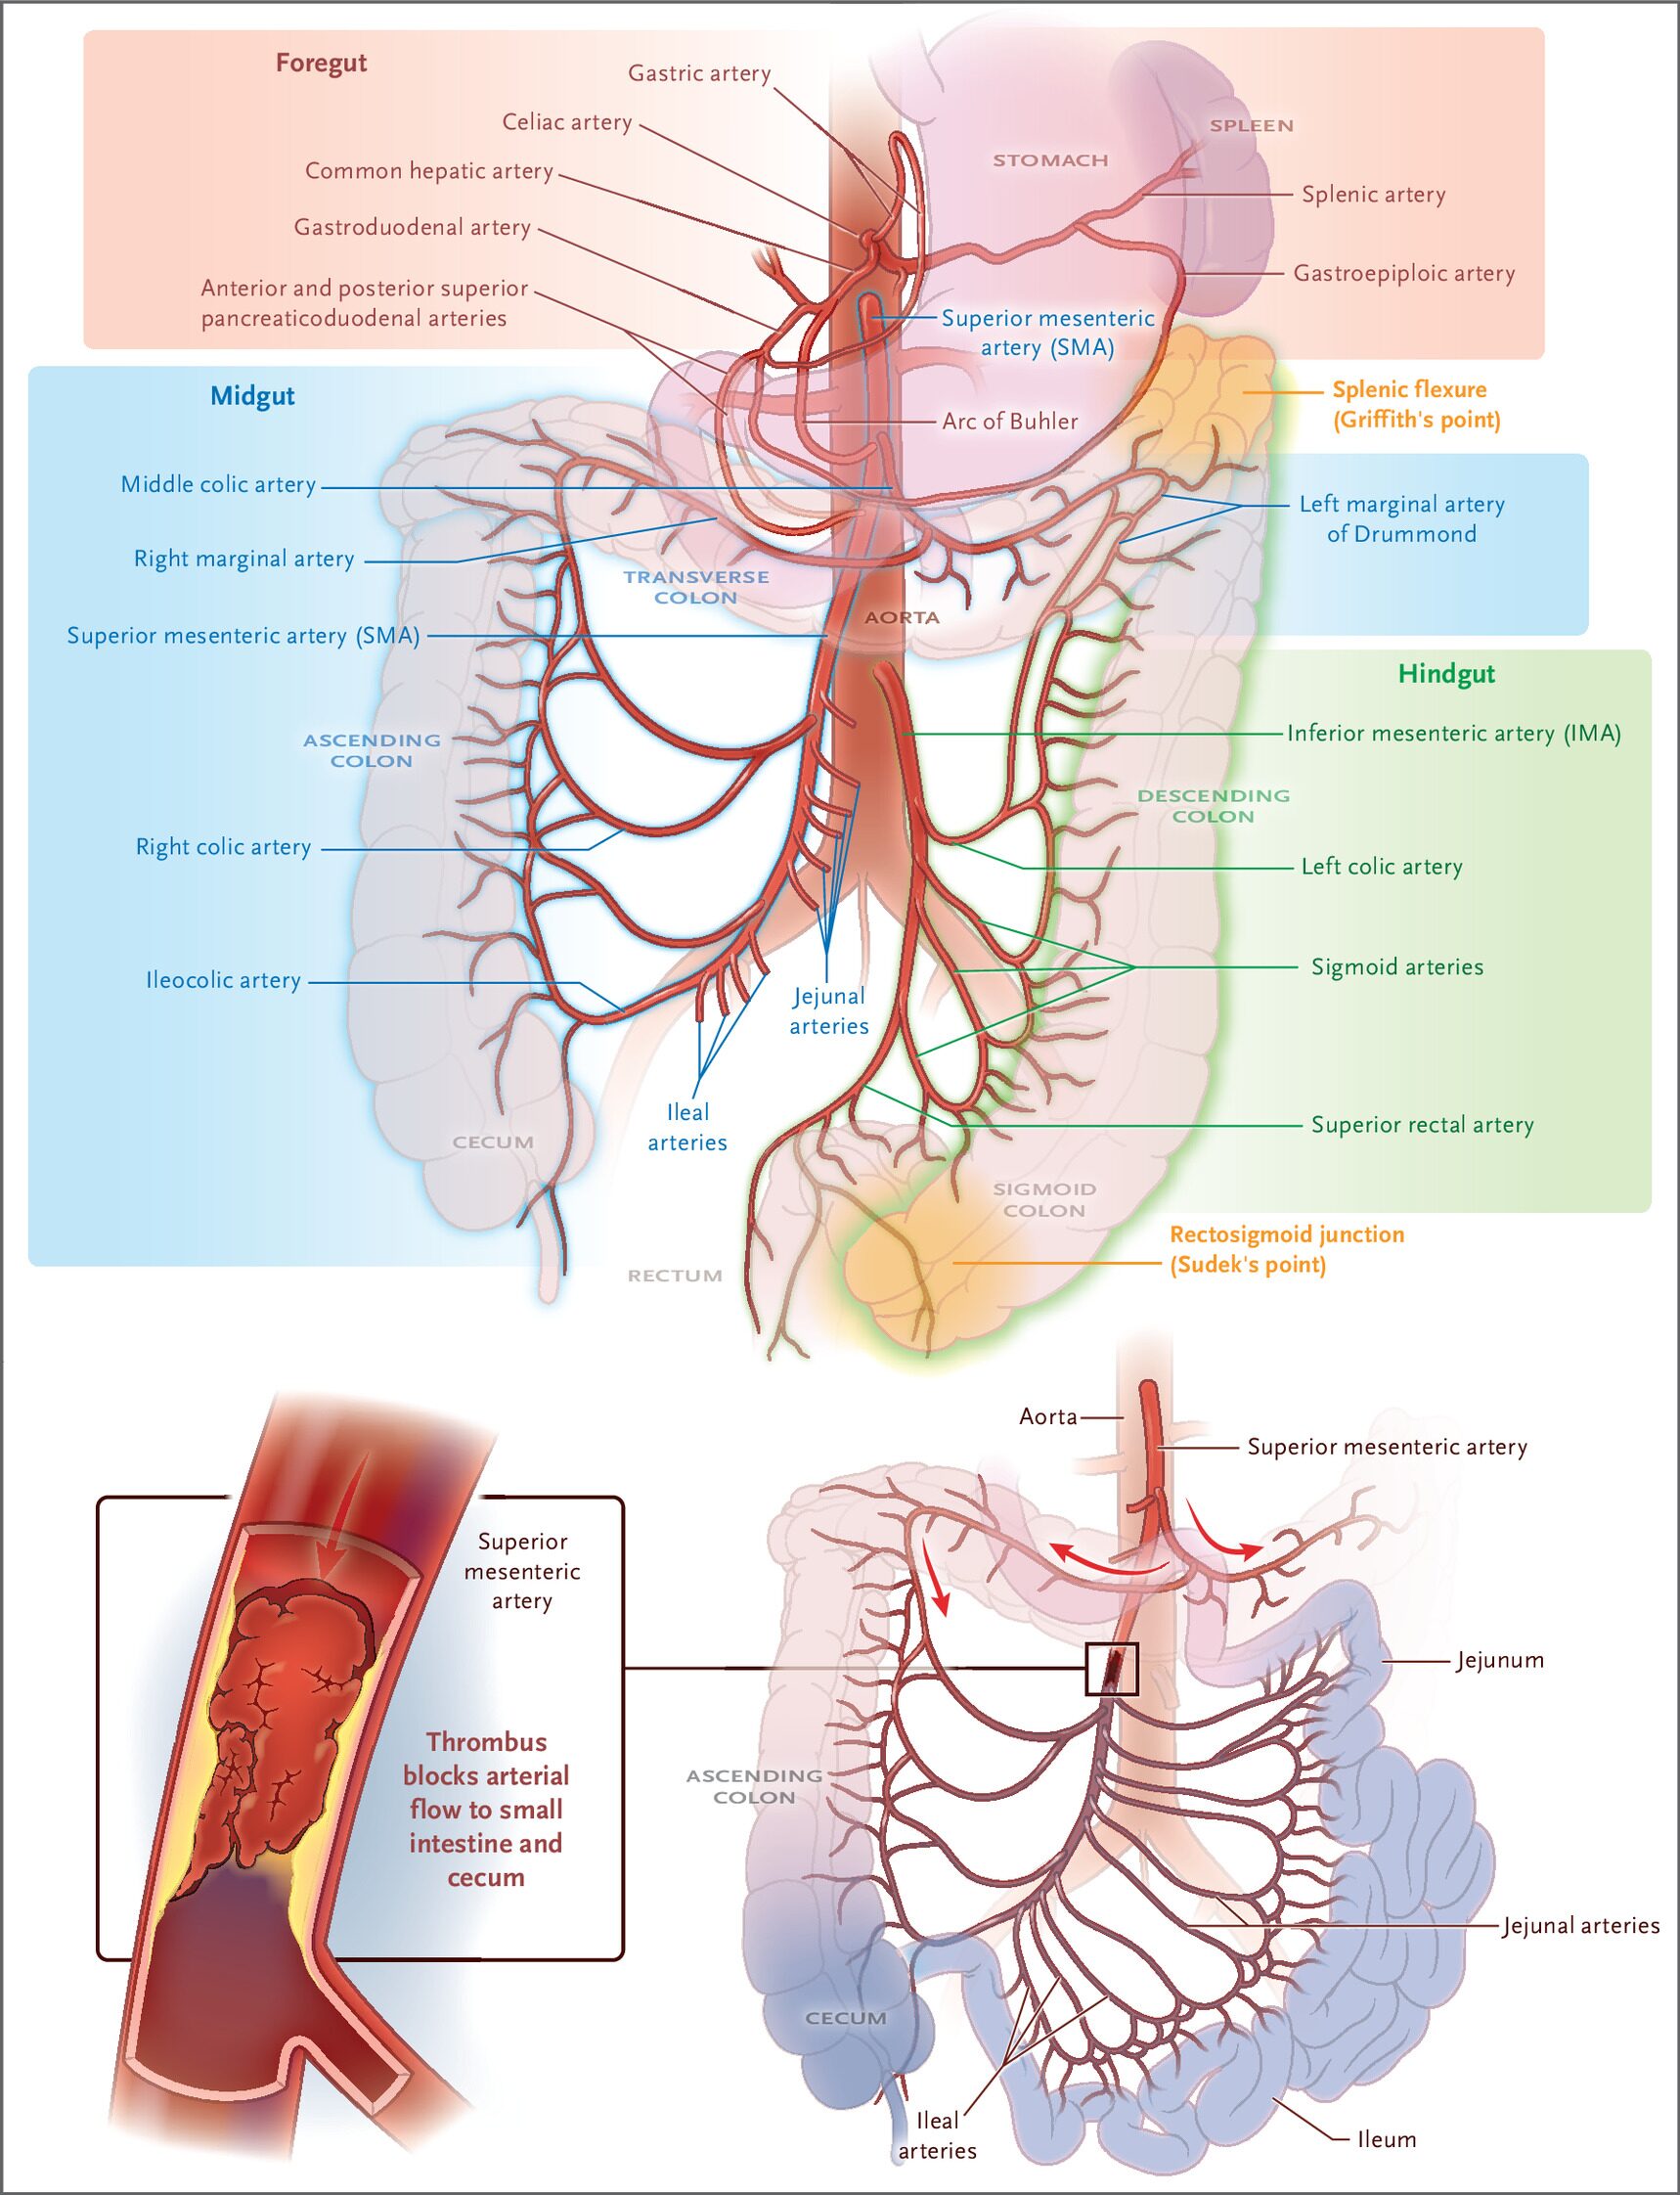

急性腸間膜虚血をきたす病態は4つ

急性腸管膜虚血とは、腸管に血液を送る血管(主に上腸間膜動脈)の血流が阻害されることで、腸管が虚血状態に陥る疾患です。頻度は緊急で手術になる症例の0.1~0.2%程度と稀ですが、致死率は50~80%と非常に高いという特徴があります。数時間で不可逆的な損傷を起こすこともあるため、迅速な診断と介入が求められる「時間との戦い」となる病態です。

■原因となる主な病態

- 塞栓による上腸間膜動脈(SMA)閉塞:心房細動などの塞栓素因がある患者に起こり、突然発症の腹部所見を伴わない重度の腹痛をきたします。

- 血栓によるSMA閉塞:動脈硬化の素因があり、ベースに慢性腸間膜虚血(食後の腹痛など)を抱える患者において、“acute-on-chronic”に腸間膜虚血が発生します。

- 門脈や上腸間膜静脈(SMV)の血栓症:静脈血栓症の素因、腹腔内感染、肝硬変や肝細胞癌などの素因がある患者で静脈に血栓ができ、還流障害により生じます。経過は突然のものから慢性経過までさまざまです。

- 非閉塞性腸管虚血(NOMI):心不全、透析、血管収縮薬の使用、脱水や低血圧などのリスク状態で、腸間膜の低灌流と血管収縮が起きて発症します。初期症状は軽度の悪心や腹痛、膨満感、せん妄など非特異的であることが少なくありません。NOMIを症状だけで診断するのは極めて困難です。